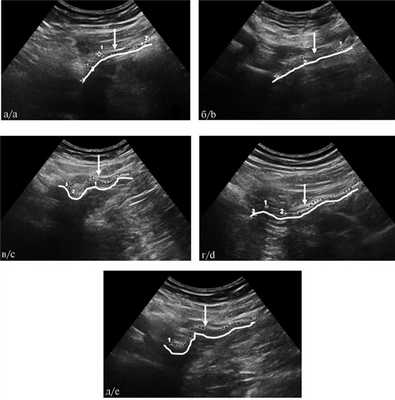

УЗИ эндопротеза выполняли в горизонтальном положении пациента на спине с помощью ультразвукового аппарата Voluson E8 (GE, США), оснащенного датчиком 3,5—5 МГц. Имплантат на всем протяжении сканировали в продольном и поперечном направлениях. Врач ультразвуковой диагностики визуализировал сетчатый имплантат, его положение относительно мышц передней брюшной стенки, лонной кости и внутреннего кольца пахового канала. На УЗИ герниопротез определялся в виде гиперэхогенной полосы различной толщины, располагающейся в проекции пахового промежутка между мышцами передней брюшной стенки и органами брюшной полости на протяжении всего пахового промежутка, перекрывающей внутреннее кольцо пахового канала (рис. 1). Рис. 1. Схема и ультразвуковая сканограмма положения эндопротеза и элементов передней брюшной стенки после правосторонней ТАРР-герниопластики. 1 — эндопротез; 2 — петли кишечника; 3 — внутреннее кольцо пахового канала; 4 — мышцы передней брюшной стенки; 5 — лонная кость.

Так, у пациентов без фиксации зндопротеза в первые сутки и через 1 мес после ТАРР-герниопластики он имеет синусоидную форму, а с 3-го месяца его форма изменяется, приобретая вид прямой, и к 12-му месяцу имплантат имеет форму практически прямой линии (табл. 3, рис. Таблица 3. Динамика формы эндопротезов по данным УЗИ в течение 1 года наблюдений (n=32) 2). Рис. 2. Изменение формы не фиксированного эндопротеза в течение 12 мес наблюдений (ультразвуковые сканограммы). а — 1 сут; б — 1 мес; в — 3 мес; г — 6 мес; д — 12 мес. Белой линией подчеркнута геометрия эндопротеза. Стрелками указан эндопротез.